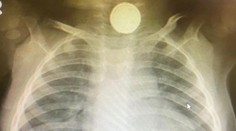

My ženy Bábätko mesiace odmietalo stravu, lekári nevedeli prečo. Všetko odhalil až röntgen Róbert Ďurkáč 14. 1. 2021